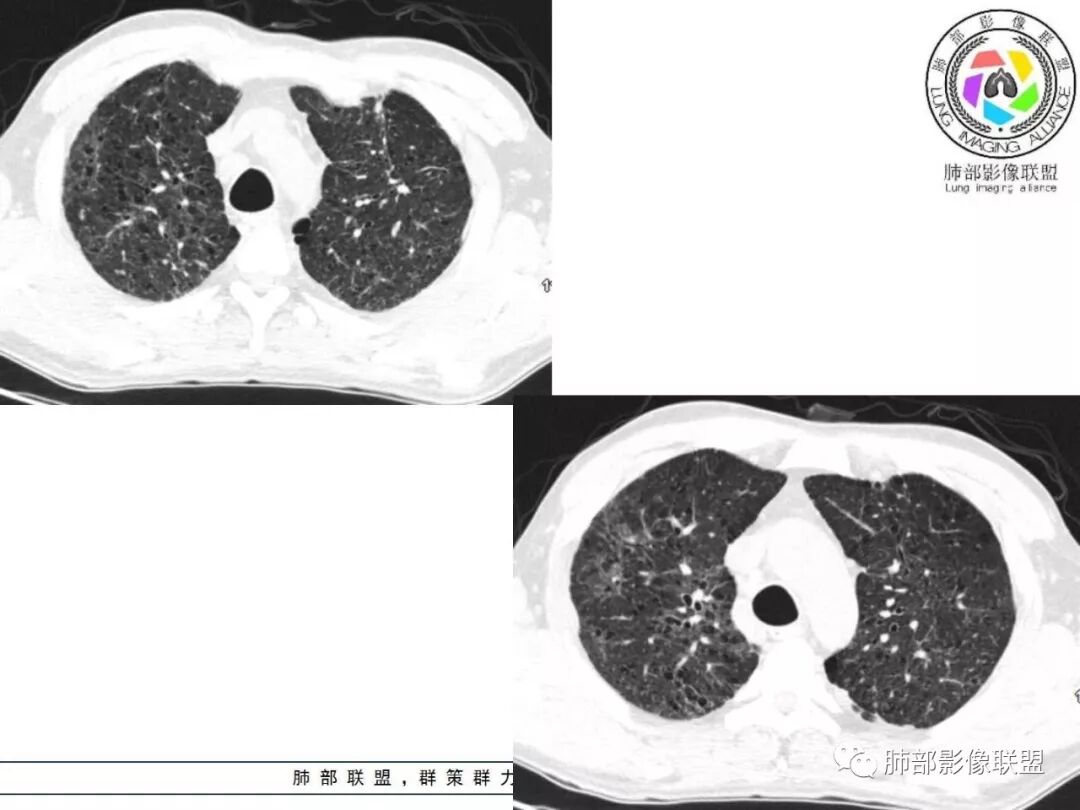

胸部CT:两肺弥漫病灶,磨玻璃影,少许实变,部分累及胸膜,磨玻璃区可见囊?少许胸腔积液,两肺可见结节,支气管血管束增粗,小叶间隔增厚,支气管走形有扭曲扩张,可见纤维化。气肿、大泡。考虑:感染性病变,PCP?查下HIV,CD4,G等。鉴别结核、结缔组织病肺浸润。

患者中年男性,发热1月,体温38℃-39℃,峰值40℃,无畏寒、寒战,伴黄痰,CRP升高明显,降钙素原稍升高,血沉、血糖正常。胸部CT:两肺弥漫病变,磨玻璃影+点片渗出,部分累及胸膜,磨玻璃区边界清楚,少许胸腔积液,两肺支气管血管束增粗,小叶间隔增厚,部分支气管走形有扭曲扩张,可见肺气肿、右肺尖肺大泡及部分纤维化改变。综合考虑:感染性病变。结核或PCP可能性大,鉴别风湿免疫、结缔组织疾病肺浸润和腺癌等恶性病变。

双肺肺气肿背景,双肺弥漫分布磨玻璃及实变密度,病灶沿血管支气管束及胸膜下分布为主,部分病灶以平直收缩为主,局部支气管稍扩张,管壁增厚,小叶间隔增厚,结合临床病史,考虑炎性病灶,感染伴病灶机化?结核?NTM?

两肺弥漫性病变,沿支气管血管束分布,部分细支气管轻度扩张,两上中肺为主,部分累及胸膜下,部分磨玻璃影,部分纤维化,肺气肿肺大疱背景,胸膜增厚,少量积液,考虑结核可能性大,鉴别op、LIP,PCP纤维化

中老年男性,发热1月余,双肺弥漫性病变,多发网格、结节、斑片状实变影及磨玻璃影,胸膜下及中轴间质都受累,支气管血管束增粗、变形,支气管扩张,叶间裂及小叶间隔增厚,整体间质性改变明显,考虑结核?OP、LIP?进一步除外PCP、肿瘤、结节病等。

病灶呈片状磨玻璃密度影,呈典型的烟花征。磨玻璃影密度偏高,有网结节样改变,与正常肺实质分界清楚,且常见相对高密度的勾画。

烟花征分为3肿类型:晕征、反晕征及均匀分布。

2. 肺气肿背景(小叶中心性肺气肿);双肺多发病灶整体沿血管支气管束及胸膜下分布,以上叶及下叶背段分布为主,有实变及GGO,边界清楚,有树芽,小叶间隔及中央间质增厚,叶间裂见到多发结节,部分支气管不规则牵拉扩张,提示病灶纤维化明显,结合临床病史,考虑病灶为间质性感染,肺门及纵隔内有钙化淋巴结,小叶间隔结节,考虑淋巴道增值性疾病可能,综合常规要怀疑间质性肺结核。